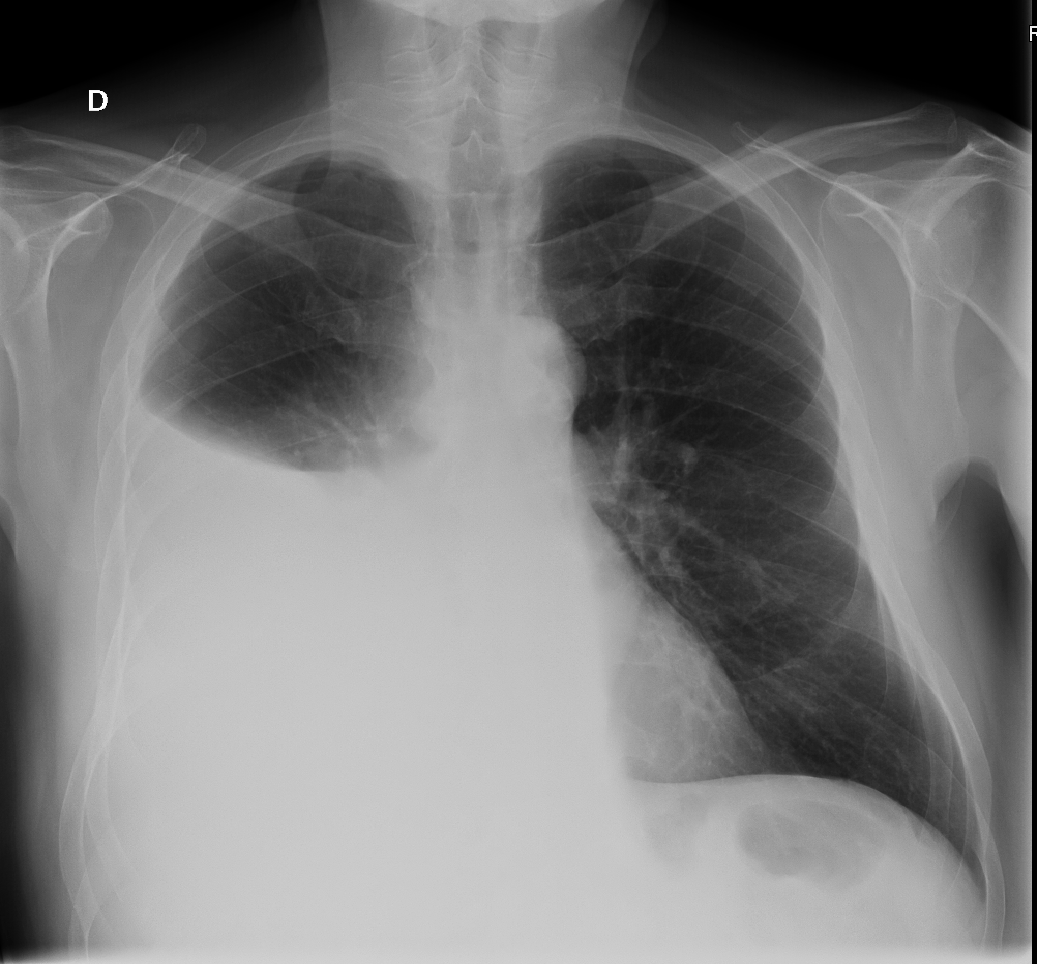

Rx torax: derrame pleural masivo que ocupa 2/3 campo pulmonar derecho.Juicio clínico, diagnóstico diferencial, identificación de problemas